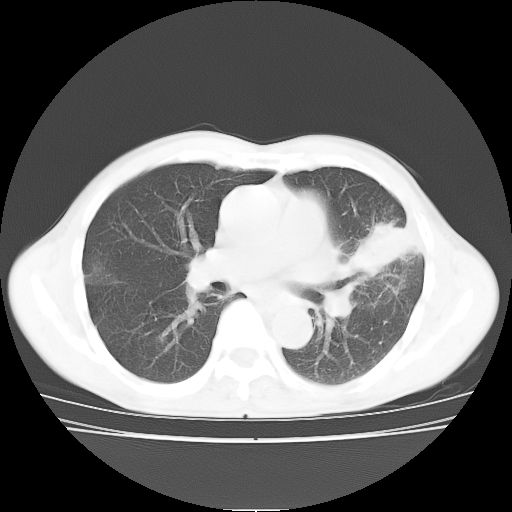

标题: CT25795:感冒后反复咳嗽两月余,痰中带血半月余。X诊断“肺 [打印本页]

标题: CT25795:感冒后反复咳嗽两月余,痰中带血半月余。X诊断“肺

1.双肺肺梗塞(理由:病灶呈三角形,与胸膜相连且局部胸膜肥厚,左心室增大)伴肺感染。

2.一元论双肺感染。

肺梗塞虽然有创意,但不现实。我考虑感染性病灶。

考虑两肺感染性病变,左肺上叶舌段肿瘤性病变待排;建议抗炎治疗后复查。